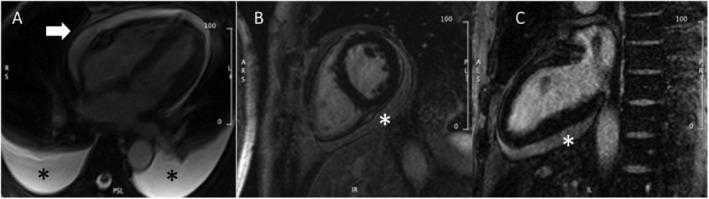

Effusive-constrictive pericarditis (ECP) is an uncommon diagnosis, frequently missed due to its heterogeneous presentation, but a potentially reversible cause of heart failure. A 62-year-old Caucasian male presented with remittent right heart failure and mild-moderate pericardial effusion. Following an initial diagnosis of idiopathic pericarditis, indomethacin was started, but the patient shortly relapsed, presenting with severe pericardial effusion and signs of cardiac tamponade, requiring pericardiocentesis. ECP was diagnosed on cardiac catheterization. Cardiac computed tomography showed non-calcified, mildly thickened and inflamed parietal pericardium. Pericardiectomy was performed with symptoms remission. On histological examination of pericardium, chronic non-necrotizing granulomatous inflammation was noted. Polymerase chain reaction assay was positive for non-tuberculous mycobacteria. This case represents a rare finding of ECP with unusual presentation due to atypical mycobacteriosis in a non-immunocompromised patient and in a non-endemic area. Pericardiectomy can be an effective option in cases unresponsive to anti-inflammatory treatment, even in the absence of significant pericardial thickening or calcification.